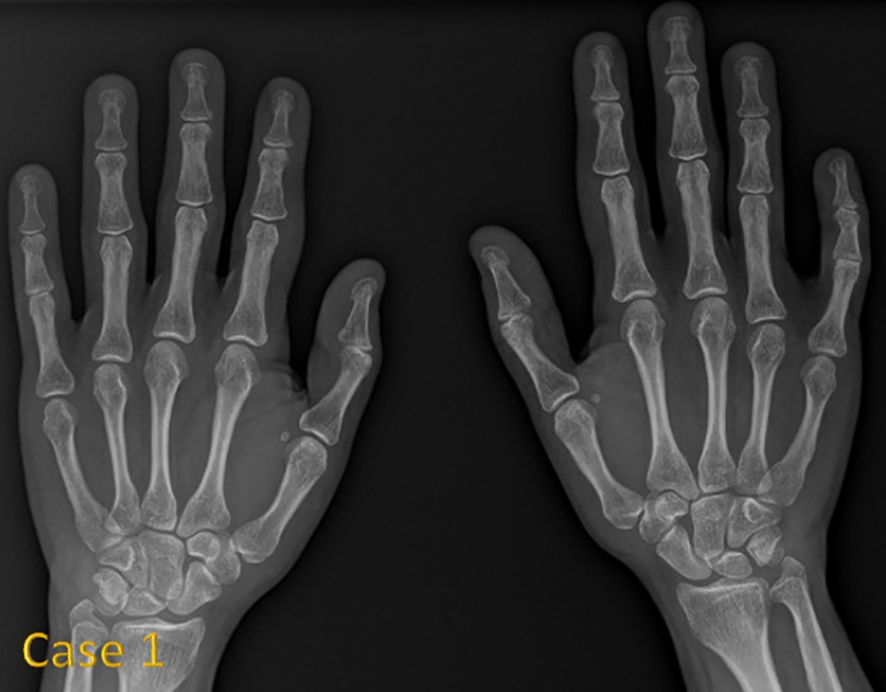

Background: 3M syndrome (3MS) is a very rare autosomal recessive disorder characterized by short stature, distinctive facial features, and skeletal abnormalities. The condition is frequently underdiagnosed due to its nonspecific symptoms and normal neurocognitive development. Few reports exist on its clinical course and response to growth hormone (GH) therapy. Therefore, this study aims to describe the clinical features of Saudi patients with 3MS and to investigate the effects of growth hormone therapy on growth. Methods: We conducted a retrospective case series of 14 Saudi patients from 11 families with genetically confirmed 3MS at King Faisal Specialist Hospital and Research Centre in Riyadh. Results: The mean age at diagnosis was 5.4 years. Consanguinity was present in 79% of cases. The most frequently affected gene was CUL7 (57% of cases), followed by OBSL1 and CCDC8. All variants were predominantly homozygous and classified as pathogenic or likely pathogenic. Clinical abnormalities included growth retardation, dental abnormalities, spinal abnormalities, and a This is a provisional file, not the final typeset article characteristic facial appearance. GH therapy was administered to 10 children; 5 demonstrated a measurable improvement in growth velocity, while 5 did not respond or discontinued treatment. IGF-1 was within/low-normal in most tested cases, with two elevated results. Conclusion: Our study highlights the extensive phenotypic variability of 3MS and underscores the predominantly autosomal recessive inheritance pattern in this population. GH therapy may provide a growth benefit in select cases, although resistance and poor response remain a challenge. Genetic testing is crucial for accurate diagnosis, individualized management, and appropriate family counseling.